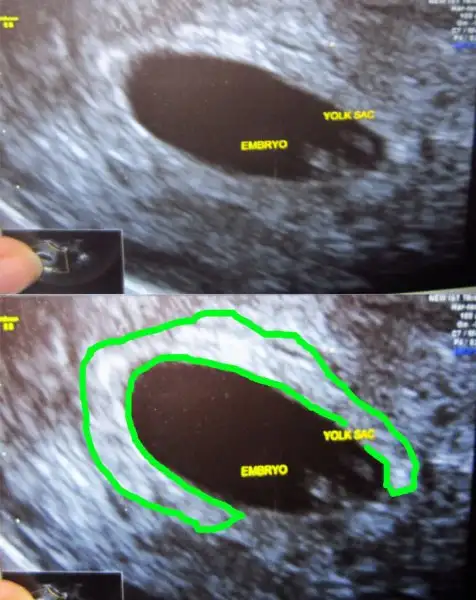

yabancı sitelere baktım canım. bebek ile plasenta daha 6 ya da 7 haftalıkken birbirinden uzak olabiliryormuş. bir kaç foto ekliyorum. bu ultrasonlar vajinal. ( bu arada bu bebişlerde plasenta yönü yani ramzi teorisi tutmuş)Cnm bu konuda bi karara varabilmemiz için burdaki plasentası sağda veya solda dediğimiz arkadaşlardan bi cvp gelmesi bizimde ona göre işe yarayıp yaramadıgını öğrenmemiz gerekiyo. Fakat çoğu daha cinsiyeti öğrenemedi galiba. Ben öğrenenlerin eski usglerine bakıorm bi kaç tane tuttu yani plasenta ve bebek solda oğlu olcakmş. Ama bi kaç tane tutması istisna olabilir canım. Ben hiçbi teoriye %100 doğru diyemem.

Evet canım bende okumuştum zaten bebekle plasentanın farklı yerlerde olduğunu biliyorum. Slvestr arkadaşımız bebek nerdeyse plasentada orda olur demişti. Ama öyle değil. Benim ilk gebeliğimde bariz bebek solda hatta en sola yapışık yani. Ama plasenta sağda ve benim 11 aylık bir cimcimem var. Yani plasenta olayı ilk gebeliğimde tuttu. Şimdi bebekte plasentada solda bakalım sonuç ne olacak. Eğer yine kızım olursa plasenta olayı yalan arkadaşlar. Tutanlar tesadüf dicez napalımyabancı sitelere baktım canım. bebek ile plasenta daha 6 ya da 7 haftalıkken birbirinden uzak olabiliryormuş. bir kaç foto ekliyorum. bu ultrasonlar vajinal. ( bu arada bu bebişlerde plasenta yönü yani ramzi teorisi tutmuş)

yabancı sitelere baktım canım. bebek ile plasenta daha 6 ya da 7 haftalıkken birbirinden uzak olabiliryormuş. bir kaç foto ekliyorum. bu ultrasonlar vajinal. ( bu arada bu bebişlerde plasenta yönü yani ramzi teorisi tutmuş)